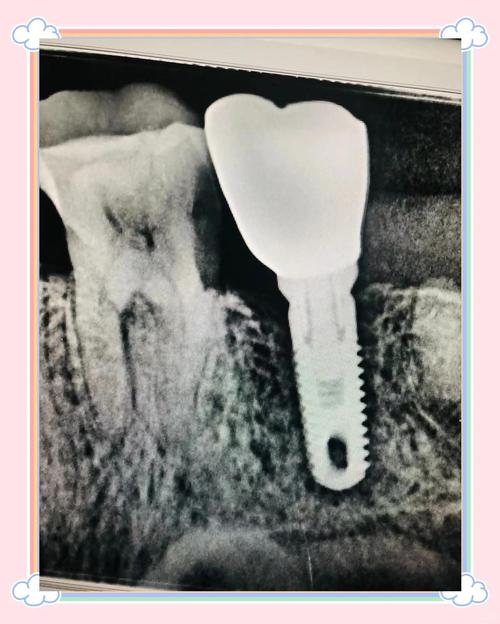

- 种植体:由生物相容性极高的纯钛或钛合金制成,通过外科手术植入牙槽骨内,其表面通常具有特殊的螺纹或粗糙结构,能与骨组织形成稳定的“骨结合”(osseointegration),成为支撑上方结构的“地基”,这部分完全位于牙龈下方和骨内,正常情况下无法被肉眼直接观察到。

- 基台:作为连接种植体与牙冠的“桥梁”,一端与种植体内部螺纹连接,另一端支撑牙冠,基台通常位于牙龈 slightly 下方或与牙龈平齐,被牙冠覆盖后同样不可见。

- 牙冠:即暴露在口腔中、模拟自然牙形态的部分,由全瓷、烤瓷或金属烤瓷等材料制成,可根据邻牙颜色、形状定制,达到以假乱真的美观效果,患者日常看到的“牙齿”,实际是牙冠,而非种植体本身。

- 定期复查:医生通过X光片检查骨结合情况,观察牙槽骨是否有吸收,同时检查牙冠磨损、基台稳定性等,确保“隐形”的种植体始终处于健康状态。

| 种植体 | 牙槽骨内 | 人工牙根,承受咀嚼力并传递至牙槽骨,支撑上部结构 | 纯钛、钛合金 | 不可见(完全埋藏) |

| 基台 | 连接种植体与牙冠 | 中间衔接部件,确保牙冠与种植体紧密咬合 | 钛、氧化锆 | 不可见(被牙冠覆盖) |

| 牙冠 | 口腔内可见部分 | 恢复牙齿形态、功能及美观,模拟自然牙外观 | 全瓷、烤瓷、金属烤瓷 | 完全可见(替代自然牙) |